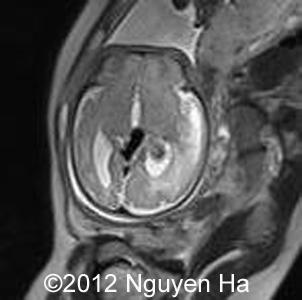

Figures 16-21:Prenatal MRI.

Figure 16-21:MRI after the first ultrasound 4 days suggesting a hematoma on the left side of the brain.